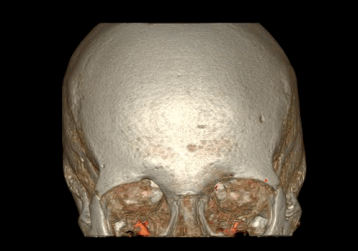

五是能谱CT去金属伪影技术

综合使用CT能谱成像技术和MARs技术,能有效减除金属植入物引起的伪影,明显改善金属植入物周围组织结构的影像清晰度,使CT图像质量显著提高,给金属植入术后患者的复查和随访提供了很大的帮助,具有广泛的临床应用价值。

GE病人列表怎么删除​【院之重器】GE Revolution 256排超高端CT:让诊断更快,更精准!_https://www.jmylbn.com_新闻资讯_第7张